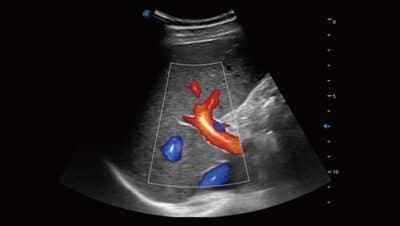

Bright Flow

Tento inovativní realistický styl pomáhá lékařům intuitivněji si představit průtok krve. Intuitivní a snadná vizualizace vzorců krevního toku s menším množstvím artefaktů krevního toku, což je užitečné při definování hranic malých cév a křížících se cév.